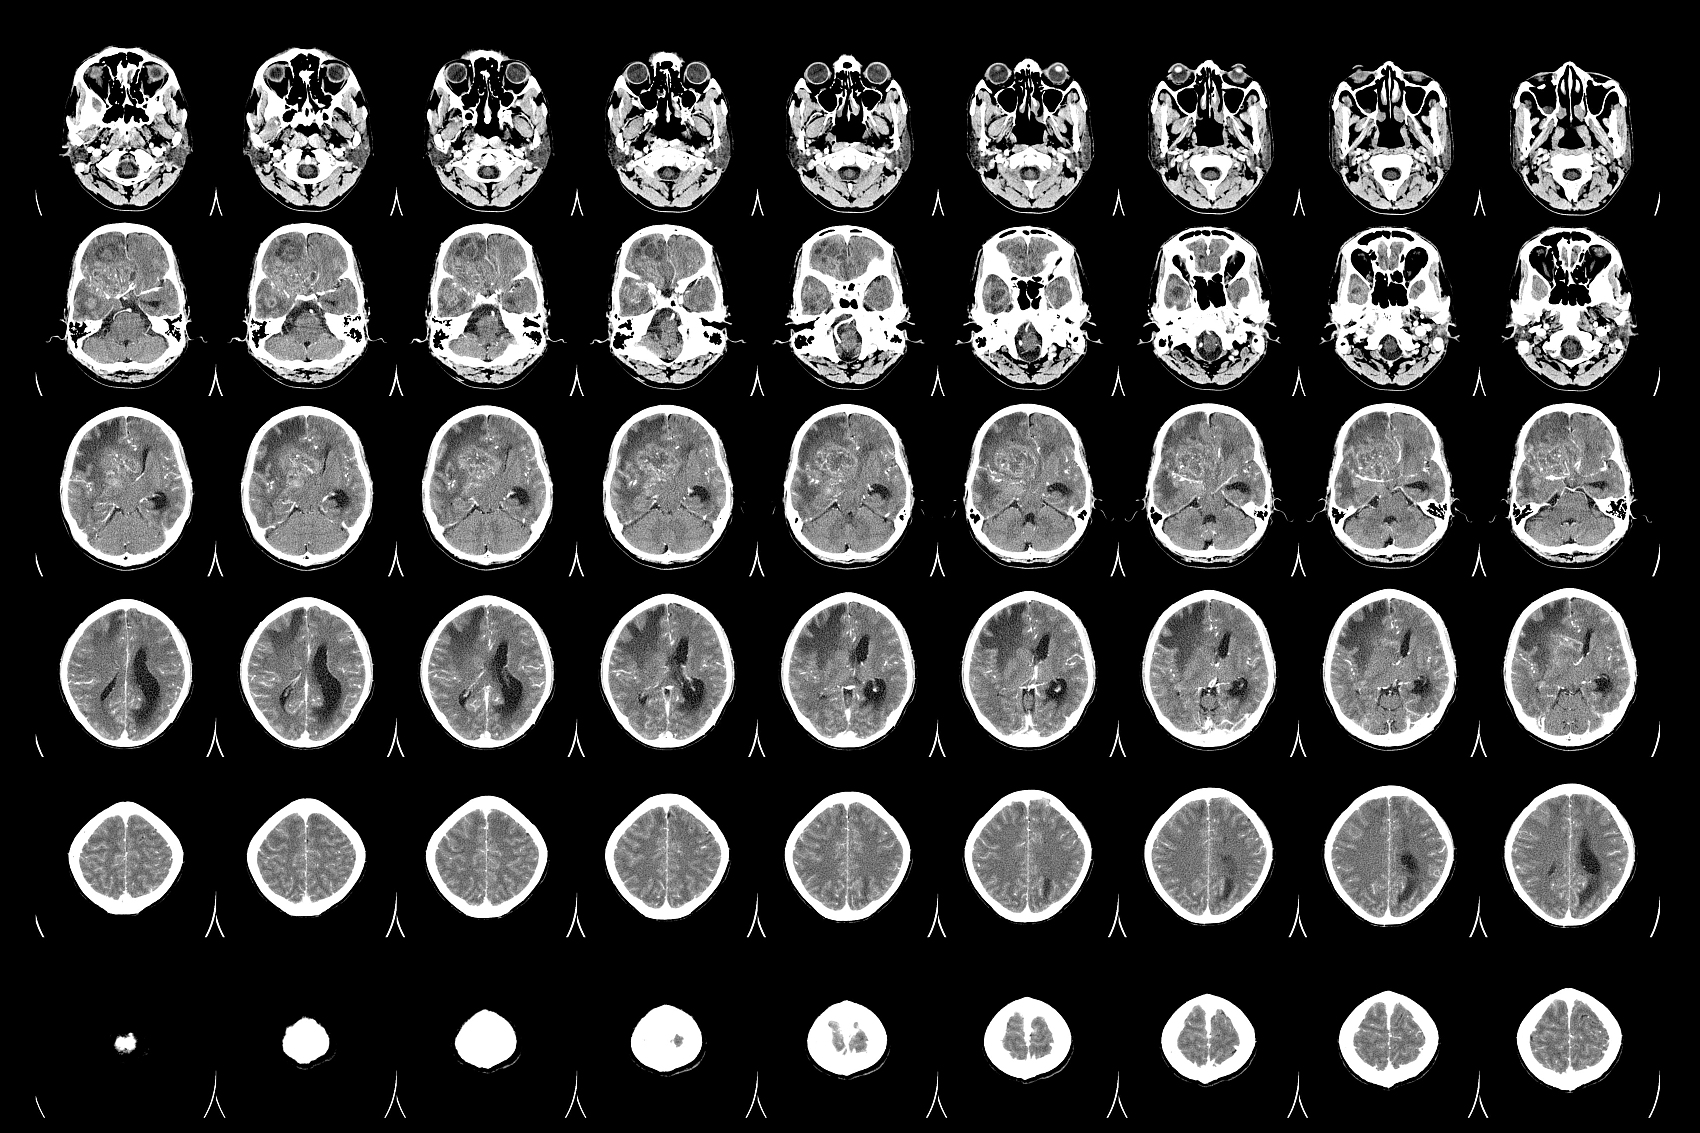

胶质瘤的临床表现在哪些方面

胶质瘤的临床表现,昆明肿瘤医院如何治疗胶质瘤-昆明医科肿瘤医院胶质瘤是一种常见的原发性脑肿瘤,其临床表现与肿瘤的大小、位置和病理类型有关。本文将介绍胶质瘤的临床表现。头痛头痛是胶质瘤最常见的症状之一,约有50%的患者会出现头痛。头痛通常是间歇性的,而且常常在早...

胶质瘤的症状,昆明治疗胶质瘤去哪家肿瘤医院-昆明医科肿瘤医院胶质瘤是一种常见的神经系统肿瘤,它起源于大脑和脊髓的胶质细胞。这种肿瘤可以是恶性的或良性的,并且可以在任何年龄段发生,但通常在成年人中更常见。本文将讨论胶质瘤的概述,包括其类型、症状和治疗。胶质瘤可以...